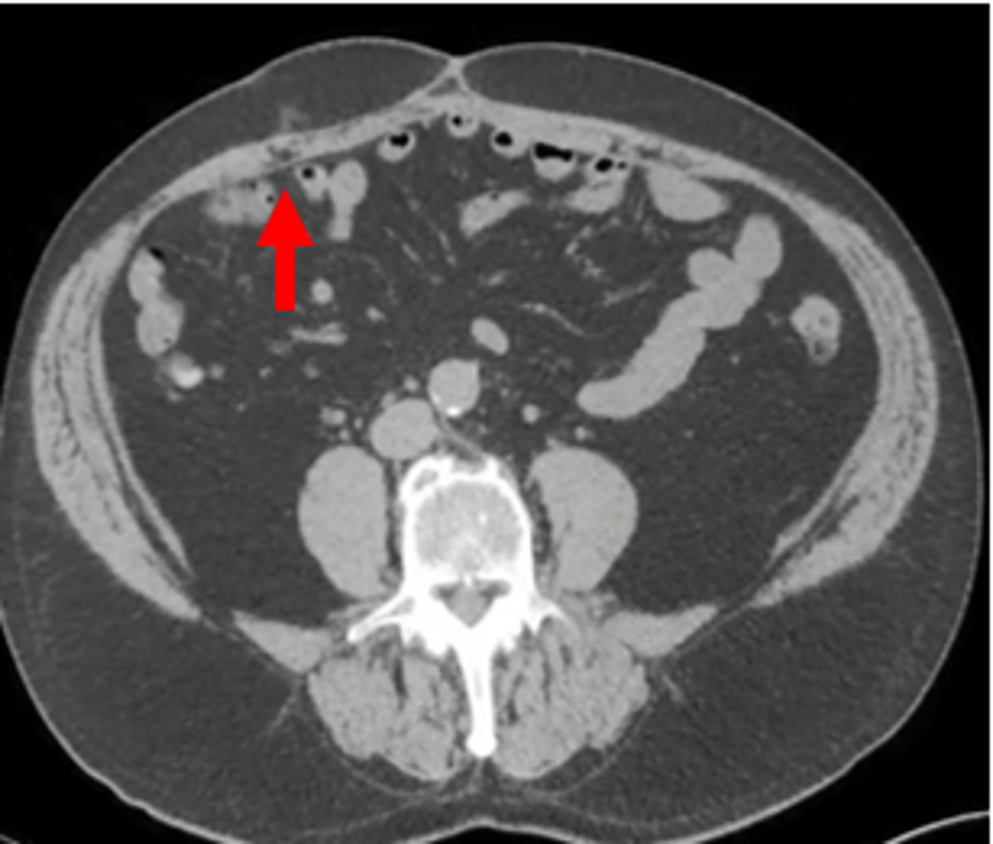

All participating radiologists were subspecialty-trained in body CT with extensive experience in postoperative CT interpretation, including a minimum of five VHR-related studies weekly. Each radiologist independently assessed 18 CT scans performed two years post-VHR. The 2- year post-operative timepoint was selected based on several considerations: (1) complete mesh incorporation and tissue remodeling typically occurs by 12–24 months, providing stable imaging characteristics; (2) this timeframe represents when many patients present with recurrent hernias requiring reoperation; and (3) it minimizes acute post-operative changes that could confound mesh visualization while maintaining clinical relevance for surgical planning. Radiologists completed a structured questionnaire to specify mesh location and type. The VHR planes were classified according to the European Hernia Society’s International Classification of Abdominal Wall Planes (ICAP) (Parker SG, et al. International classification of abdominal wall planes (ICAP) to describe mesh insertion for ventral hernia repair. Br J Surg. 2020;107(3):209–217). The planes assessed included: (1) retrorectus plane - mesh positioned posterior to the rectus muscle and anterior to the posterior rectus sheath; (2) retromuscular plane - accessed only after transversus abdominis release (TAR), with mesh extending laterally beyond the semilunar line; (3) preperitoneal plane - mesh positioned between the peritoneum and transversalis fascia; and (4) intraperitoneal plane - mesh placed within the peritoneal cavity (Fig. 1). All meshes used in this study were permanent synthetic polypropylene and categorized by density. Heavy-weight synthetic mesh (HWSM) was defined as PROLENE® Mesh, manufactured by Ethicon with a density of 95 g/m² (Fig. 2). Medium-weight synthetic mesh (MWSM) referred to Bard™ Soft Mesh, with a density of 43 g/m², and light-weight synthetic mesh (LWSM) corresponded to Ultrapro™ advanced, with a weight of 26 g/m² (Figs. 3 and 4) Detailed characteristics for all 18 cases, including mesh specifications and CT parameters, are provided in Supplementary Table 1. Additionally, the study incorporated CT scans from two control groups: a negative control group with patients who had never undergone abdominal surgery, and a positive control group with patients who had undergone laparotomy without VHR. Control CT scans were obtained at variable timepoints: positive control scans (laparotomy without VHR) were acquired 3–6 months postoperatively to capture healed surgical changes without mesh, while negative control scans (no prior abdominal surgery) had no timing restrictions as they served to demonstrate normal abdominal wall anatomy. The 3–6 month timepoint for positive controls was selected to ensure complete laparotomy healing while avoiding long-term tissue remodeling that might obscure surgical plane distinction. While this creates temporal mismatch with 24-month VHR scans, the primary diagnostic task focuses on mesh presence/absence rather than temporal evolution of surgical changes. This timepoint captures healed surgical changes without mesh-related artifacts, providing appropriate control for radiologist assessment. All radiologists were informed of the inclusion of these control scans in the study.

Fig. 3

Medium Weight Mesh

Bild vergrößern